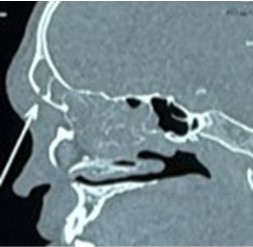

Kết quả chụp CT mũi xoang phát hiện viêm đa xoang bên phải nhiều hơn trái. Đặc biệt, hình ảnh CT xác nhận tổn thương viêm lan từ xoang trán phải ra phần mềm vùng trán, kèm hình ảnh khuyết xương ở thành trước xoang trán phải — bằng chứng hình ảnh học điển hình của biến chứng Pott’s Puffy Tumor (PPT). Đồng thời ghi nhận vẹo vách ngăn mũi trái và quá phát cuốn mũi dưới hai bên.

Hình: CT scan mũi xoang ghi nhận viêm đa xoang và vùng hủy xương thành trước xoang trán (P).